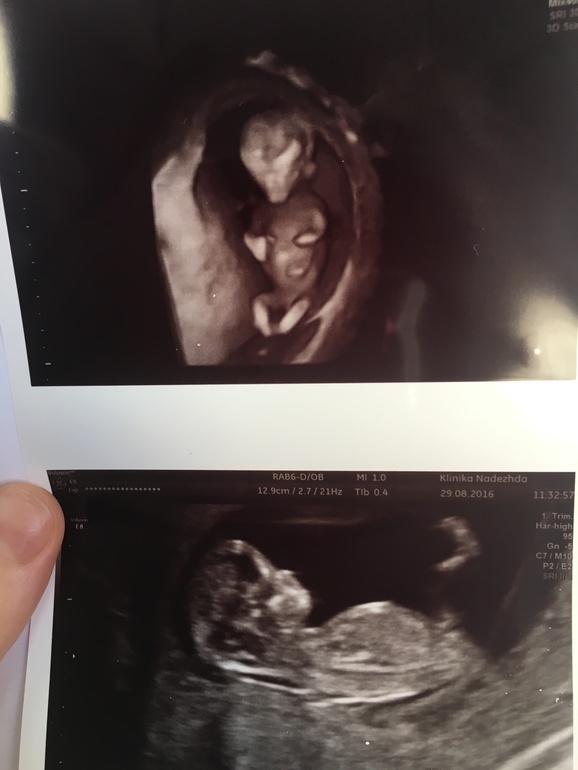

По месячным 22.2, по узи поставили ровно 22 недельки . Весим мы 526 гр, рост 28 см 🥰Девочка осталась девочкой 😌 доказательство тоже сняли 😉 все хорошо с малышкой , растём , развиваемся🙏🏻